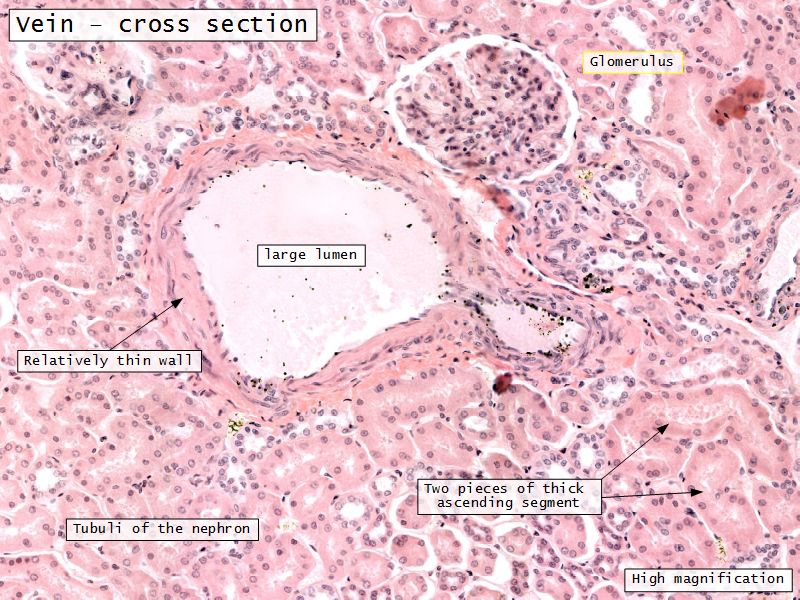

- Interlobular arteries/veins

Blood flow

- Efferent arteriole

- Smooth muscle in media

- Capillaries

- Fenestrated

- Afferent arteriole

- Smooth muscle in media